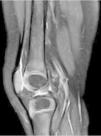

Antibiotic treatment was initiated with endovenous cloxacillin and cefotaxime with progressive improvement of clinical and radiological symptoms (Fig. 2).